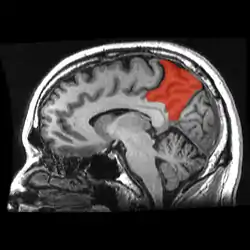

|  Sagittal MRI slice with the precuneus shown in red. (Anterior to the left.) | |